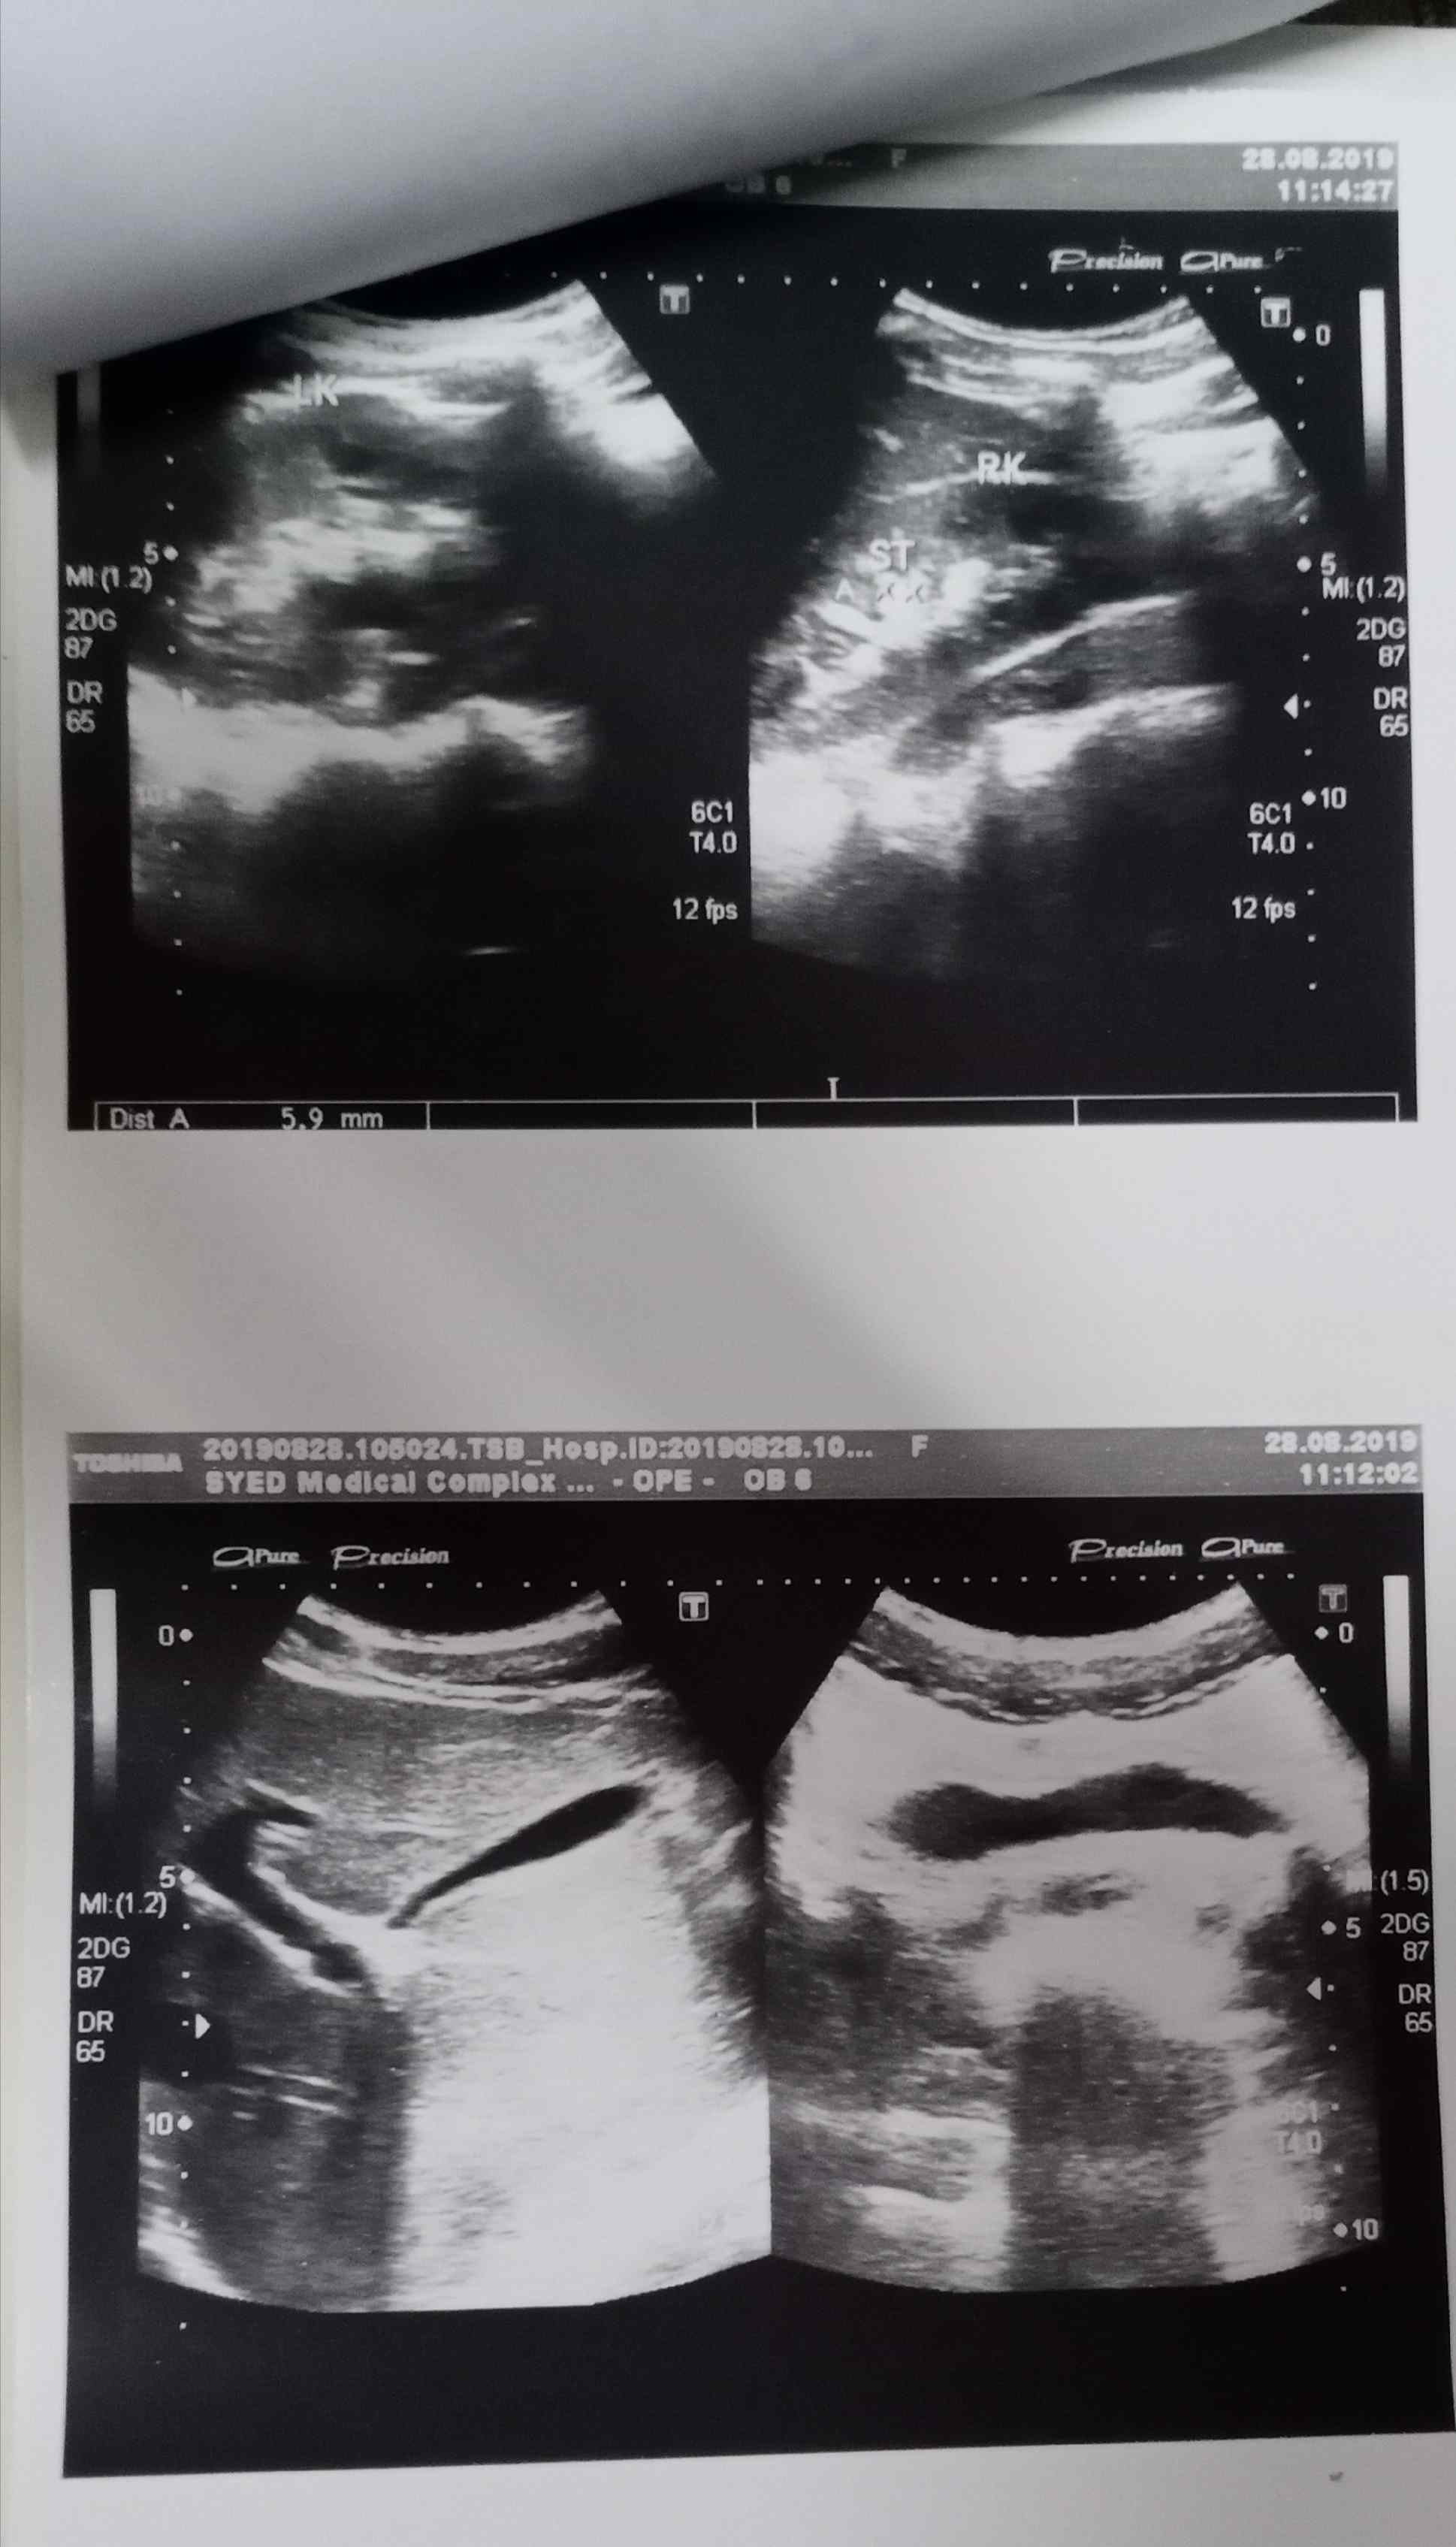

Attach Photo here: